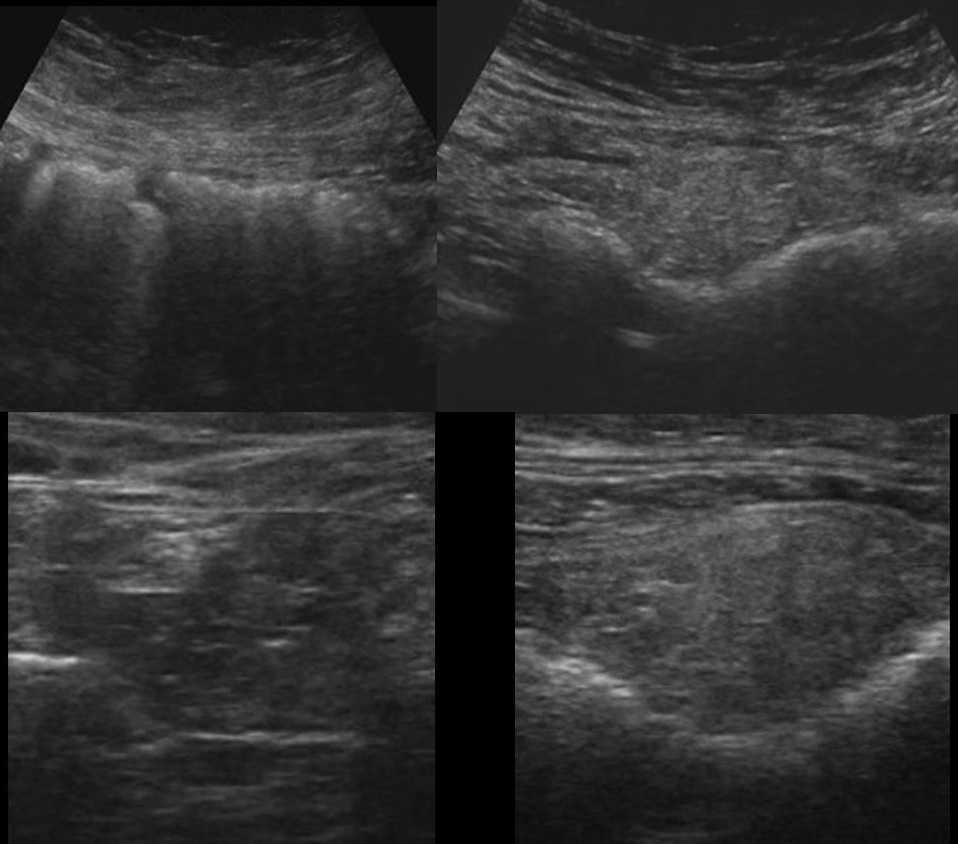

Инфаркт большого сальника на УЗИ

Больший сальник представляет собой двухслойную перитонеальную структуру, состоящую в основном из сальниковых сосудов и жировых тканей. Он прикрепляется к большей кривизне желудка и проксимальной части двенадцатиперстной кишки, как фартук прикрывает тонкую кишку, заворачивается на уровне входа в малый таз и возвращается к поперечной ободочной кишке. Сальник называют «полицейским» живота, так как он сдерживает распространение инфекции и опухолей.

Если случается перекрут фрагмента сальника, то развивается острое нарушение кровообращения. Предрасполагающие факторы: ожирение, кашель, физическая нагрузка, а так же тромбофилия, застойная сердечная недостаточность, васкулит и аномалии строения сосудов сальника. Спонтанный инфаркт в 90% случаев поражает правый нижний сегмент сальника, самый подвижный и богатый жиром. Когда инфаркт является осложнением воспалительных процессов, хирургического лечения, ущемления грыжи или травмы, то поражение может располагаться в разных участках брюшной полости.

Инфаркт сальника часто путают с острым аппендицитом, инвагинацией, брыжеечным лимфаденитом. Признаки этих заболеваний включают боль в правом нижнем квандранте живота, напряжение мышц брюшной стенки, рвоту.

В большинстве случаев инфаркт сальника разрешается без специального лечения. Поврежденный участок отграничивается и претерпевает инволюцию, главным образом с фиброзом, иногда с кальцификацией, редко возникает абсцесс. Некротический фрагмент может отделится и свободно фланировать в брюшной полости.

На УЗИ между передней брюшной стенкой и поперечной или восходящей ободочной кишкой определяют несжимаемую умеренно гиперэхогенную массу овальной или треугольной формы. Эхоструктура чаще неоднородная за счет гипоэхогенных очагов: аваскулярные трубчатые структуры — сосуды, зоны с нечеткими контурами — геморрагический инфаркт. Иногда поражение окружено анэхогенным ободком «хало» — жидкость. При ЦДК кровоток чаще не определяется, но у детей может сохранятся кровоток по периферии. Почти всегда находят умеренное количество жидкости в брюшной полости.

Рисунок. На УЗИ нормальный сальник (1, 3) неотличим от окружающих тканей. При инфаркте сальника (2, 4) прямо под передней брюшной стенкой определяется неоднородная умеренно гиперэхогенная зона с четким контуром.

Рисунок. Мальчик в течение 2-х дней жалуется на боль внизу живота справа. На УЗИ (1, 2) в точке максимальной болезненности определяется яйцевидная несжимаемая гиперэхогенная масса (стрелка), эхоструктура неоднородная за счет гипоэхогенных участков; при ЦДК единичные сигналы в центре и усиление кровотока на периферии. Заключение: Ультразвуковой симптомокомплекс может соответствовать сегментарному инфаркту большого сальника. Через 1 день состояние ребенка резко ухудшилось, на УЗИ (3, 4) васкуляризация в области поражения отсутствует. Проведена лапароскопическая оменэктомия.

Рисунок. Женщина с сильной болью внизу живота и рвотой. На УЗИ в области максимальной болезненности (правая подвздошная ямка) определяется овальной формы несжимаемая гиперэхогенная масса, неоднородная за счет гипоэхогенных участков, размер 92x30x57 мм; кровоток в пределах поражения отсутствует. Очаг примыкает к передней брюшной стенке и отграничен от кишечных петель. Смежные мелкие и крупные кишечные петли нормальной эхоструктуры. Аппендикс не изменен. Небольшое количество жидкости в правой подвздошной ямке. Заключение: Ультразвуковый симптомокомплекс может соответствовать инфаркту большого сальника. Для уточнения диагноза рекомендовано КТ.